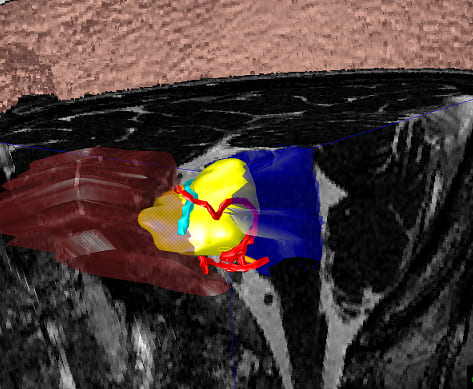

内耳道における微小解剖

聴神経腫瘍手術シミュレーション

内耳道内限局腫瘍と脳神経